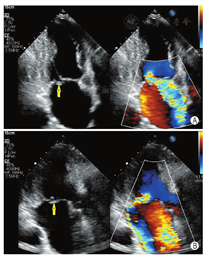

通过采集以下切面显示二尖瓣瓣叶各扇区。①胸骨旁左室长轴切面:显示A2、P2(图5A);②二尖瓣水平短轴切面:显示整个前后叶(图5B);③心尖四腔心切面:显示A2、P2(图6A);④心尖长轴切面:显示A2、P2(图6B);⑤心尖二腔心切面:显示A1、P3(图7A);⑥心尖二尖瓣交界处长轴切面:显示P1、A2、P3(图7B)。

TTE通过上述切面评价MR的机制、程度以及部位,并确定瓣膜运动异常的扇区。